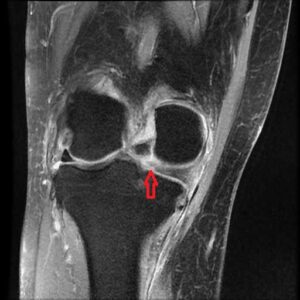

2週間たっても痛みが軽くならない膝痛は、MRIなどの精密検査をお勧めします。

MRI MMPRT 20251117